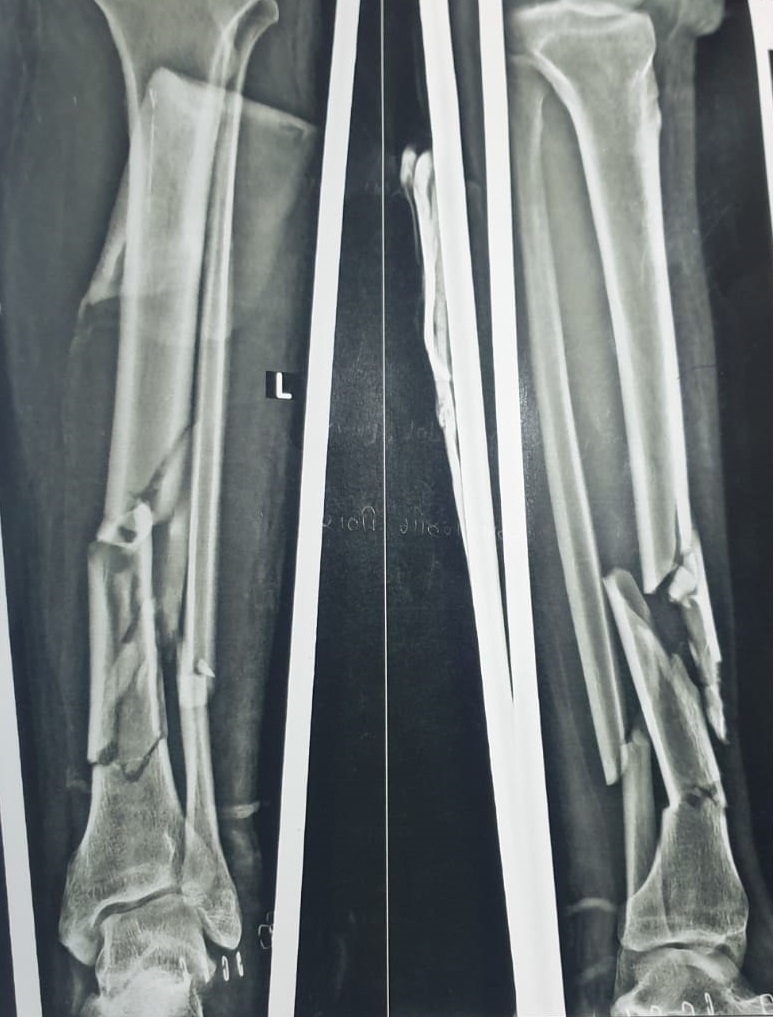

Preoperative Findings:

Radiological evaluation revealed multiple fracture segments in the midshaft region with loss of structural continuity. The Samay Surgical Pvt. Ltd.’s Expert Tibia Nail was chosen for its high mechanical strength and ability to support complex shaft injuries effectively.

The patient presented with a Diaphyseal Segment Fragmentary Fracture—a break involving several segments along the tibial shaft, typically requiring robust internal fixation.